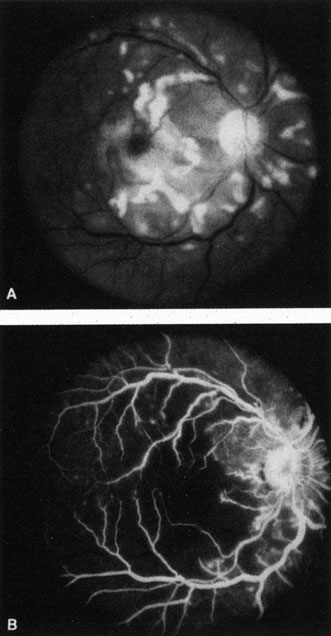

Cilioretinal arteries can be selectively obstructed (Fig. 3). More commonly, however, they occur in association with central retinal vein obstruction.113 When they supply a significant portion of the macula, decreased visual acuity is common. Prognosis for visual outcome in such patients is good. Brown and co-workers114 studied 10 eyes having an isolated cilioretinal artery obstruction. Of those, 60% had an initial visual acuity of 20/40 or better and on follow-up examination, all eyes but one had a best-corrected visual acuity of 20/40 or better.114

Fig. 3. A: Cilioretinal artery obstruction showing opacity of the retina in the area of obstruction. B: The cilioretinal artery has begun to fill after the branches of the central retinal artery but is still not completely filled at this point in the angiogram.

Fig. 5. A: Ischemic optic neuropathy in a patient with giant cell arteritis. B and C: Intravenous fluorescein angiography demonstrates delayed filling of the lateral posterior ciliary artery.

We have seen several patients with anterior ischemic optic neuropathy with suspected temporal arteritis where the Westergren sedimentation rate and C-reactive protein were normal and the intravenous fluorescein angiogram helped confirm the diagnosis (Fig. 5).